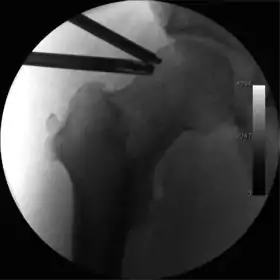

Figure 5. Portal placement under direct vision. The instrument is entering the joint through the hip capsule, between the femoral head (on the left) and acetabular labrum (on the right)

The next step is to insert a fine needle under x-ray guidance into the hip joint. This breaks the 'suction seal' of the joint and allows further distraction if necessary (see fig 4). The surgeon wishes to see the ball move out the socket by approximately 1 cm, so that access to the hip joint can be achieved with minimal risk of damage to the joint surfaces. Most surgeons will inject fluid into the joint at this stage, again to ensure that there is enough space between the ball and socket for safe instrument access. This needle is then removed. The next step is placement of the 'portals', or the small holes made to pass instruments into the joint. This is achieved by again passing a fresh hollow needle into the joint under x-ray control, usually in a slightly different position. The reason for this is so the surgeon can ensure that the needle, and subsequent cannulae do not penetrate and damage the acetabular labrum or cartilage joint surfaces (see fig. 5). Again, surgeons will have their own preferences as to their preferred placement. Through this hollow needle, a long thin flexible guide wire is passed into the joint, and the needle is removed over it, leaving the guide wire in situ. A small cut in the skin is made around the wire, to allow for larger cannulae to be placed over the wire through the portal. The wire therefore guides the larger cannulae into the joint. The most common external diameters of cannulae used are between 4.5 and 5.5 mm. Once the surgeon is satisfied that the cannula is in the correct position, by a combination of feel and x-ray guidance, the guide wire can be withdrawn. Once the first portal is correctly placed, any further portals may be created once the camera is in position, to ensure that they are placed with minimal risk to the joint surfaces. This process can be repeated to gain as many points of entry to the hip joint as the surgeon requires, normally between two and four. Certain of these entry points will be used for the viewing arthroscope and others for operating instruments.